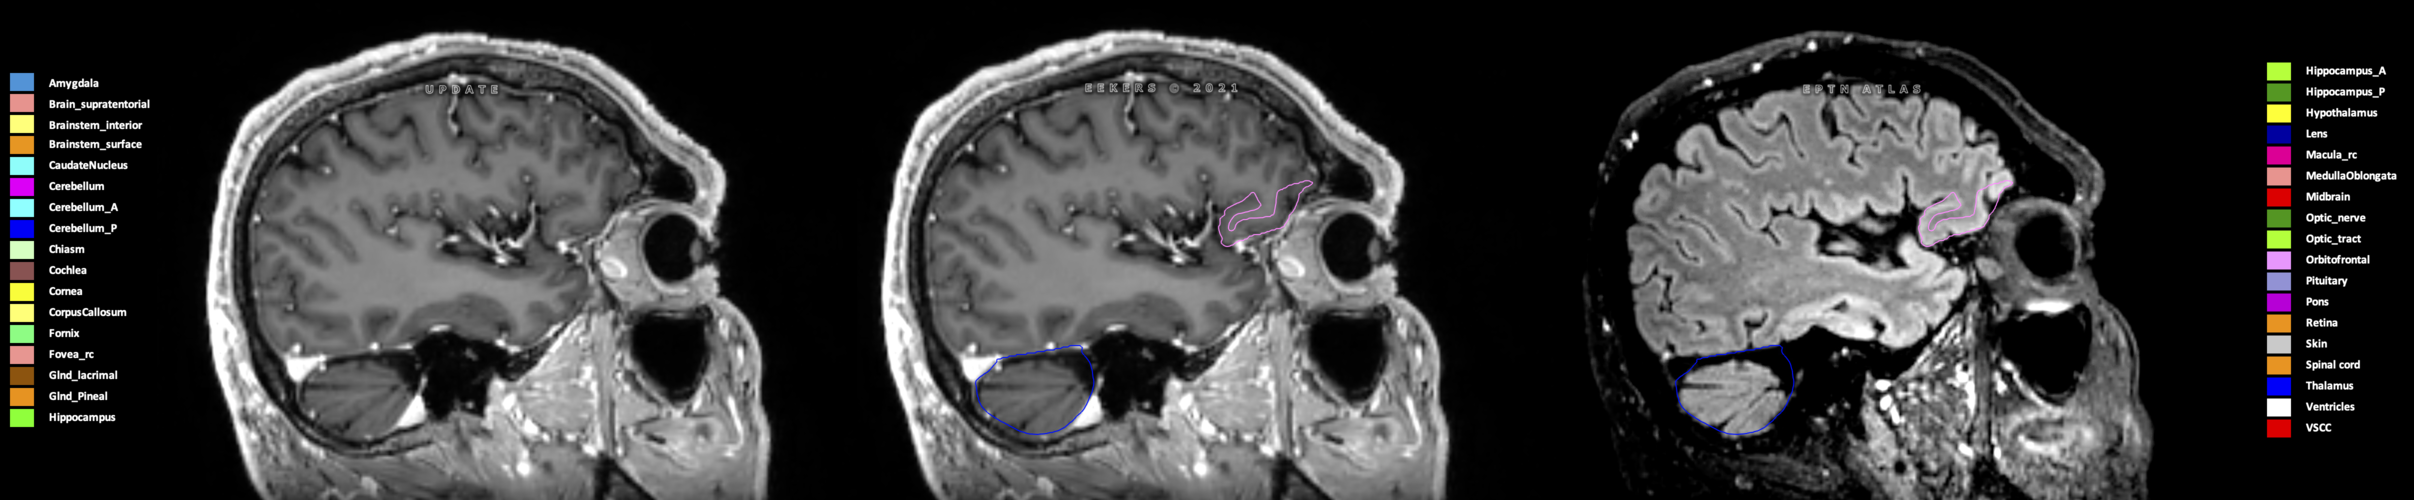

Eekers et al. have published an international neurological atlas for contouring of organs at risk in consensus with the European Particle Therapy Network (EPTN) in 2018 and an update in 2021. The purpose of this consensus atlas is to decrease inter- and intra-observer variability in delineating OARs relevant for neuro-oncology.

Included are all OARs known to be relevant for radiation-induced toxicity in neuro-oncology: brain, brainstem (midbrain, pons, medulla oblongata), chiasm, cerebellum (anterior & posterior), cochlea, cornea, hippocampus (anterior & posterior), hypothalamus, lens, lacrimal gland, optic nerve, pituitary, skin, and vestibular & semicircular canals. To further facilitate research on cognition, vision and radiological changes after irradiation of the brain, potential clinically-relevant OARs are included: amygdala, caudate nucleus, cerebellum (anterior & posterior), corpus callosum, fornix, macula, optic tract, orbitofrontal cortex, periventricular space (PVS), pineal gland, and thalamus.

Three-dimensional delineation of the 25 consensus OARs for neuro-oncology are shown on CT (WW/WL 120/40, 3000/600), 3T MR images, (T1Gd, T2FLAIR 1mm) and 7T MR (MP2RAGE 0.7 mm). All are presented in transversal, sagittal and coronal view.